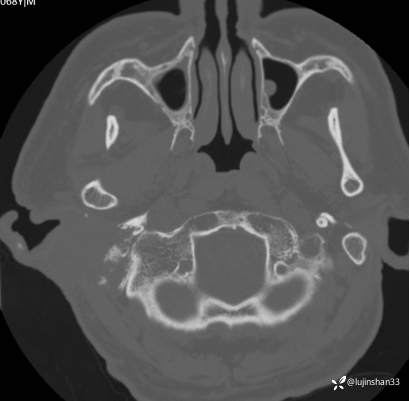

CT:

简要病史:患者2022年10月掏耳后出现右耳疼痛,流水,伴血性分泌物,伴听力下降,无头痛头晕,无口角歪斜,自行购买滴耳液及口服罗红霉素,效果不佳。后右耳痛加剧,偶需止疼药治疗。后于XXXXXX医院行中耳乳突CT检查示“右耳恶性肿瘤?坏死性外耳道炎?”颅脑磁共振平扫示“脑内多发缺血灶、梗塞灶,脑白质疏松,脑萎缩、右中耳恶性占位。”建议上级医院治疗。2023-4-13就诊于我科门诊,行右外耳道病理活检示“鳞状上皮黏膜慢性炎伴急性炎,可见较多炎性坏死,部分上皮增生明显伴不典型增生,小灶上皮呈重度异型增生伴癌变。”建议手术治疗。今患者为求进一步诊治,门诊以“颞骨占位(右)“收治入院。

右侧颞骨鳞癌(T4)